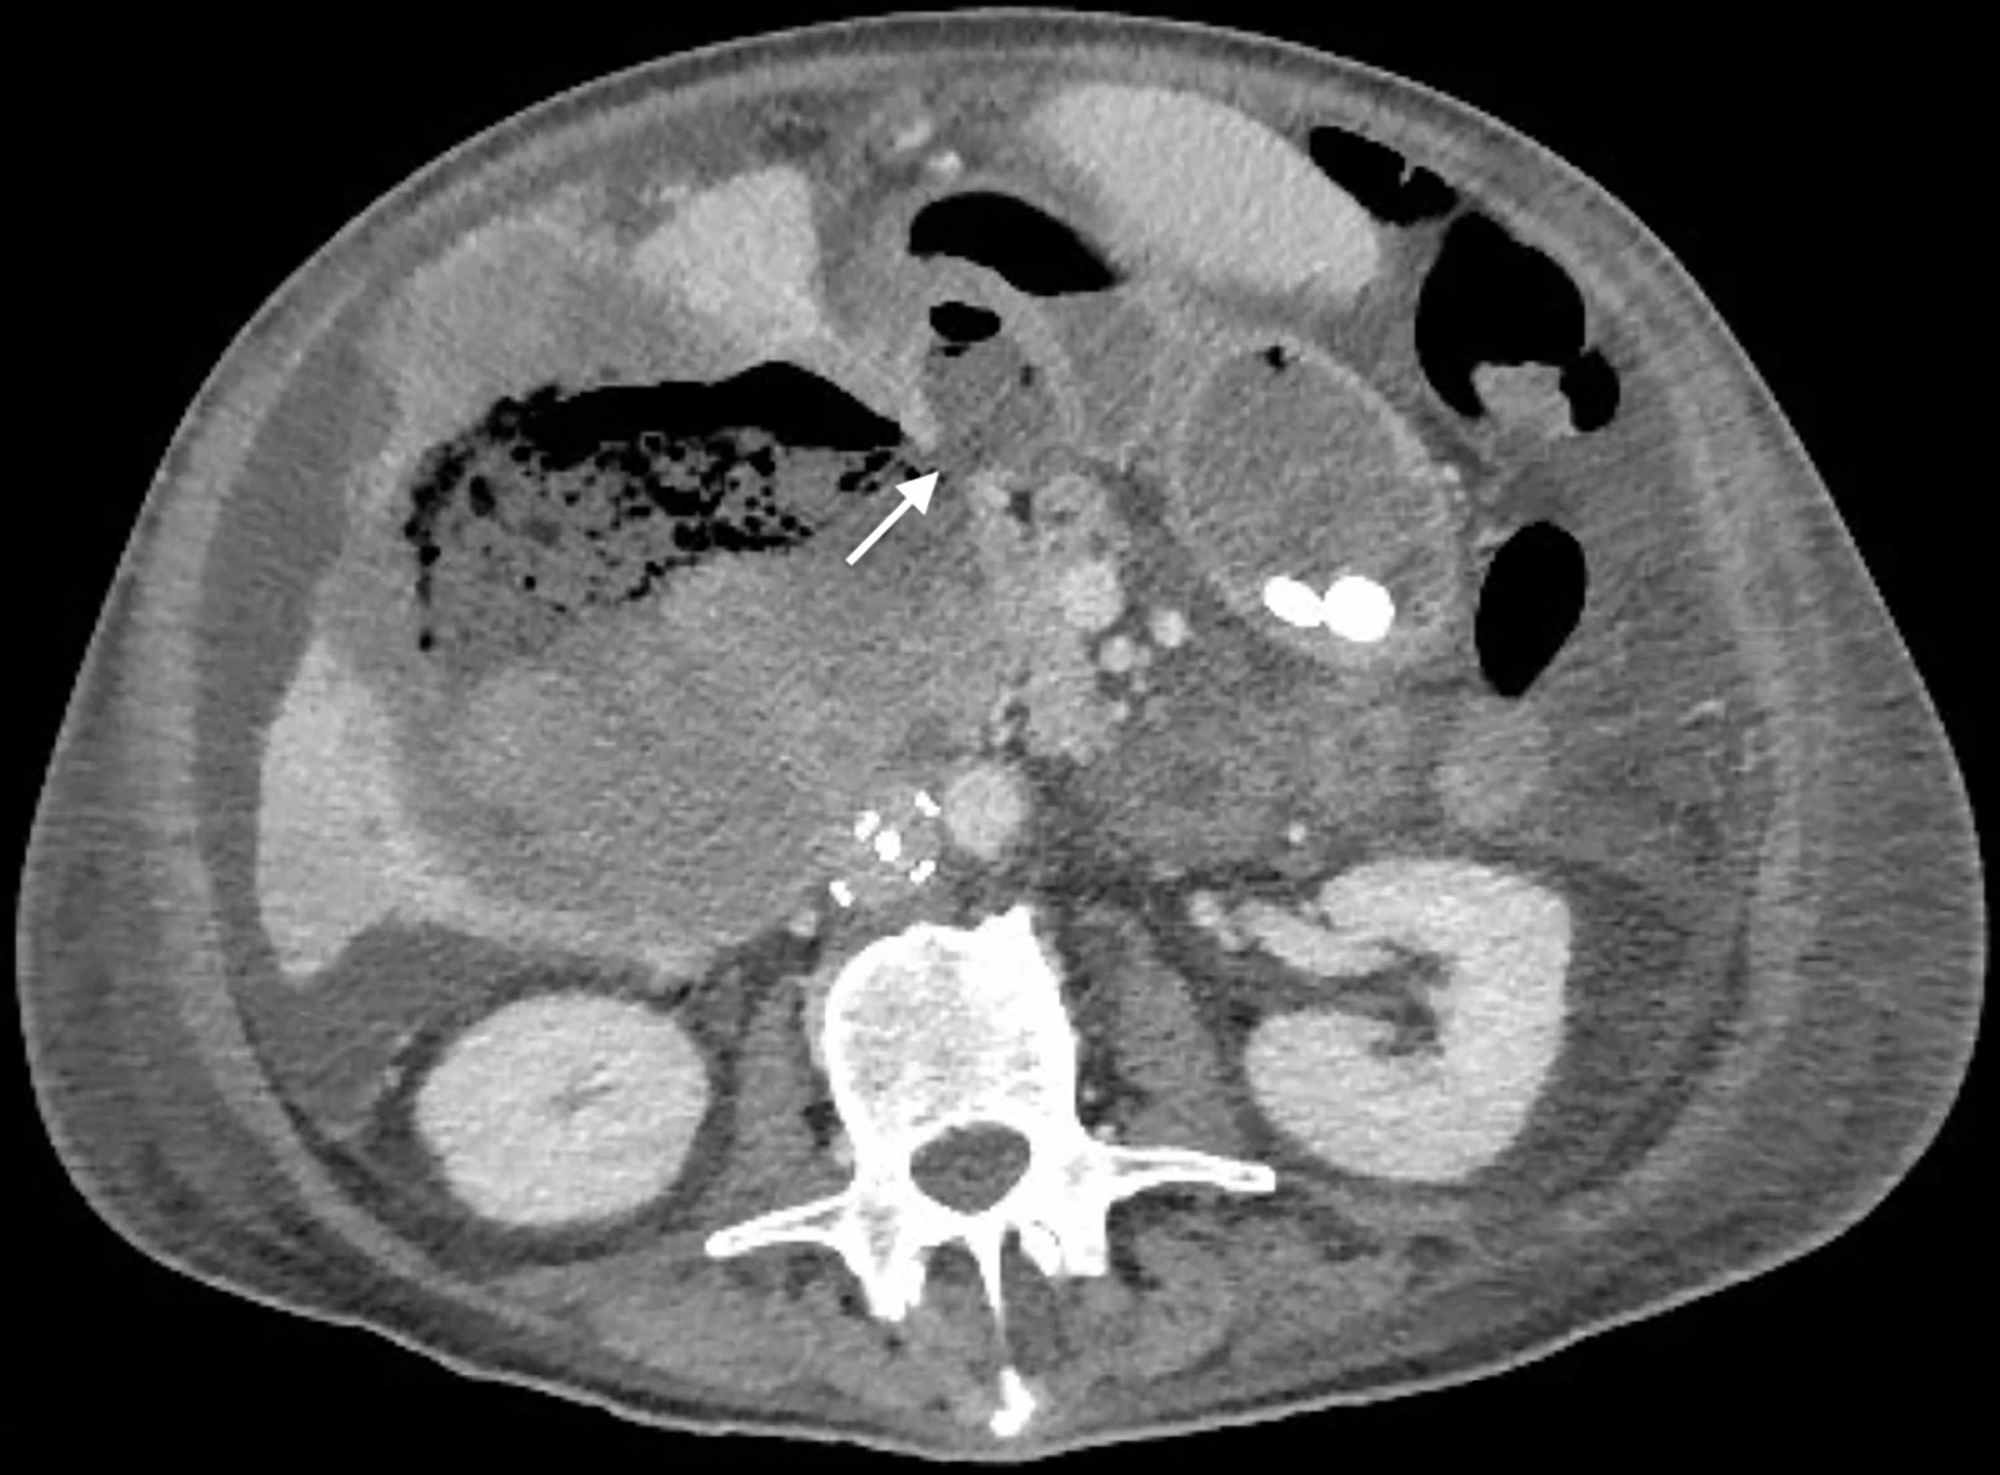

Squamous cell carcinoma of the skin. Wasserman, md ●adrian m 1from the department of radiology, university of minnesota, minnesota veterans administration mous cell carcinoma (1). Squamous cell carcinoma accounts for only 3 to 7% of bladder cancers in western countries, but in certain countries where parasites are very common (especially schistosomiasis) it is found much more frequently.

Squamous cell carcinoma of the urinary bladder is a malignant neoplasm derived from bladder urothelium with pure squamous phenotype.

Which can arise from a urachal remnant? Squamous cell carcinoma of the urinary bladder is a malignant neoplasm derived from bladder urothelium with pure squamous phenotype. It is associated with keratinizing squamous metaplasia. The diagnosis of squamous cell carcinoma of the bladder should be reserved for those tumors that are predominantly keratin forming.